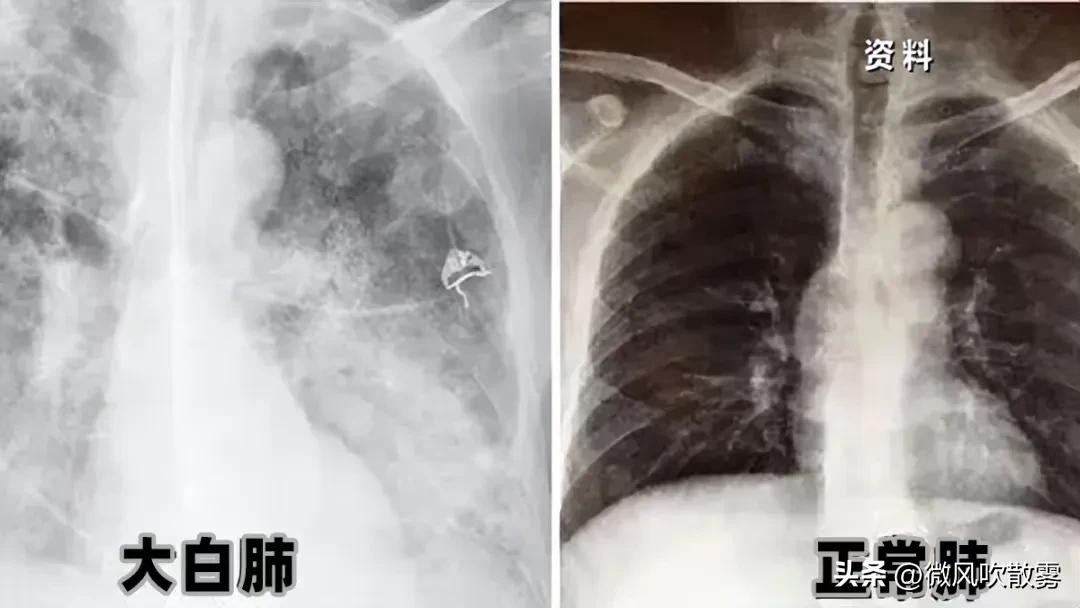

那么,什么叫白肺?白肺也不是疾病的词汇,就是近几年,肺部因为一些病变(比如发炎)出现的磨玻璃影,这种现象的一个统称。

也并不是所有肺炎都叫“白肺”,“白肺”是比较严重的肺炎表现,白色的影像区域面积达到了70%到80%。如此会影响肺的呼吸功能和血氧浓度,也就是容易出现呼吸窘迫和低氧血症。